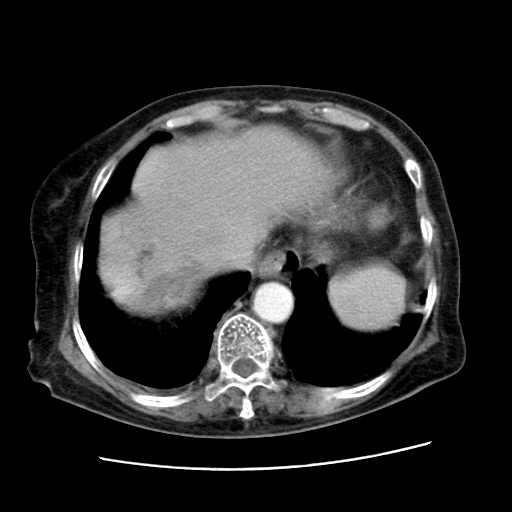

女,77.无不适

肝脏变异、异位胆囊,肝右叶肝内胆管结石并肝内胆管扩张。

肝内胆管扩张,胆囊炎,胆囊窝积液。 右侧胸腔少量积液。

肝脏变异

肝右叶肝内胆管结石并肝内胆管扩张

胆总管扩张

右侧胸腔少量积液(也可能是胸膜增厚不过是什么都一样)

胆囊未见明显显影

肝右叶肝内胆管结石并肝内胆管扩张。胆总管下段梗阻,考虑壶腹部占位。

右侧肝内胆管局限性扩张,其内密度不均匀,扩张的胆管壁增厚,考虑肝内胆管炎合并结石可能性大